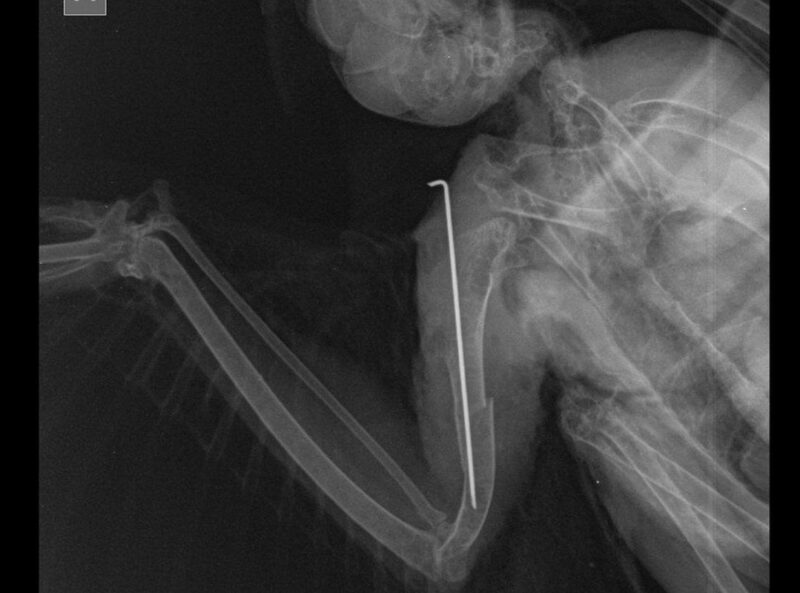

– Мы сделали рентгеновский снимок, на котором виден открытый перелом правого крыла со смещением мягких тканей. Поэтому пришлось провести остеосинтез кости. Говоря простым языком, в крыло птице была введена осевая спица, которая поможет тканям срастаться, – рассказывает ветврач.

Павел Жульпа поясняет: птицы очень тяжело переносят наркоз, однако в данном случае операция прошла успешно. Ястреб пришел в себя и уже несколько дней находится в стационаре клиники под круглосуточным наблюдением врачей.

– Ястреб должен быть ограничен в движении до тех пор, пока кости не срастутся. На это может уйти от нескольких недель до двух месяцев. А когда наступит пора, Сапсанчика вновь привезут в Лиду, чтобы снять с крыла спицы, – поясняют в Центре спасения животных.